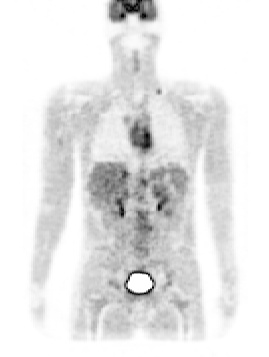

Construction of a realistic 3D PET whole-body image database

Our aim was to generate and distribute a realistic database of simulated whole body [18F]FDG PET oncology images. OncoPET_DB (http://www.creatis.insa-lyon.fr/oncoPET_DB) provides 100 realistic simulated [18F]FDG PET images with (50 cases) or without (50 cases) inserted lesions. As far as we know, this database is the first addressing the need of simulated [18F]FDG PET oncology images by providing a series of whole-body (WB) patient images with well controlled inserted lesions of calibrated uptakes. It also will fulfil the requirements of detection performance studies by including normal and pathological cases. The realism of the database is based on three points: firstly, we built a complex model of [18F]FDG patient based on the Zubal phantom in combination with activity distributions in the main organs of interest derived from a series of 70 clinical cases. Secondly, we proposed a realistic model of lesions extent corresponding to lymphoma patients. Finally, the simulated database was generated with the PET-SORTEO Monte-Carlo simulation tool that was fully validated against the geometry of the ECAT EXACT HR+ (CTI/Siemens Knoxville).

Figure 2. left: coronal slice through the Zubal phantom with inserted lesions (red points). Middle: simulated PET image corresponding to the Zubal model. Right: superimposed label model and PET simulated data.